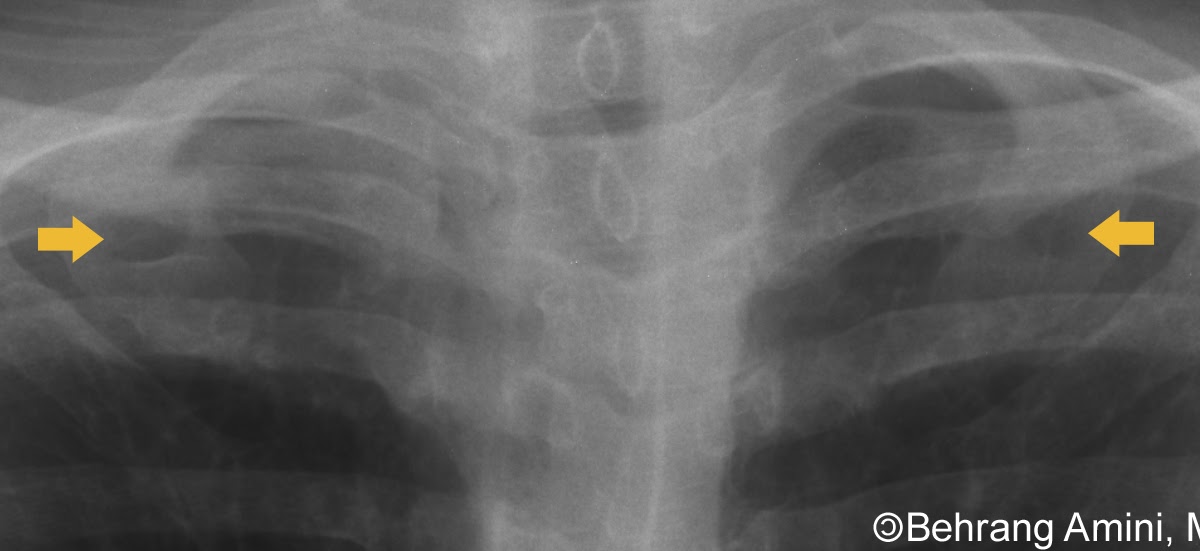

Pneumopericardium after ICD placement on chest xray. Mild